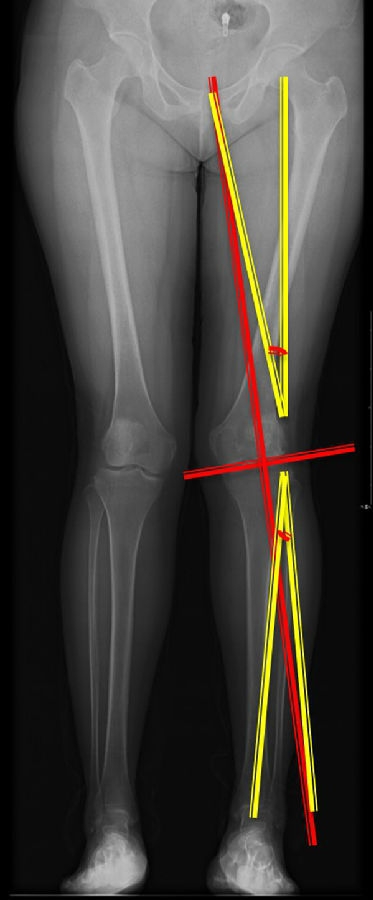

以两例病例展示术前设计的五步。患者一,女性,42岁,左膝疼痛2年,加重1年。

步骤一:判断内外翻畸形

画下肢机械轴,股骨头中心链接踝关节中心判断患者为内翻畸形还是外翻畸形。此患者为外翻畸形。

步骤二:判断畸形部位

量股骨远端外侧角和胫骨近端内侧角,判断畸形在股骨、胫骨还是关节内。此患者股骨侧有畸形,LDFA=76°,MPTA=81°,无关节内畸形。

步骤三:设定目标力线

以关节线为基准参考线,设定目标力线与关节线垂直。

步骤四:确定合页位置和截骨线方向

此患者计划股骨内侧闭合楔,胫骨内侧开放楔。

步骤五:Miniaci法测量角度

以股骨侧合页为旋转中心,以股骨头中心到合页的距离为半径,进行旋转,直到该线段与目标力线相重合,此时重合角度即为股骨需要闭合的角度,同时胫骨侧也能计算出开放的角度。此患者需要股骨闭合14°,胫骨开放8°。